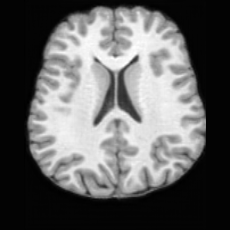

PathologicalHealthyDifferencew/o ACGw/ ACG(a)Refer to captionRefer to captionRefer to captionRefer to captionRefer to captionHealthyPathologicalDifferencew/o ACGw/ ACG(b)Refer to captionRefer to captionRefer to captionRefer to captionRefer to caption

Figure 6: Ablation study of Anatomy Consistency Guidance (ACG): (a) pathology-to-healthy; (b) healthy-to-pathology. Without ACG, edits cause anatomical inconsistencies outside lesions (arrows), whereas ACG keeps modifications lesion-focused.

Anomaly Consistency Guidance. Fig. 6 demonstrates the effectiveness of the proposed Anatomy Consistency Guidance (ACG) on bidirectional editing. Without ACG, the generated brains exhibit noticeable and unrealistic anatomical deformations in non-lesion regions (arrow-indicated), leading to structural inconsistencies between the edited and original brains, as shown in the corresponding difference maps. After incorporating ACG, the model effectively constrains editable modifications within pathological regions, while preserving the remaining anatomy. Tab. 4 further reports their quantitative performances: removing ACG leads to a substantial degradation in all L1, PSNR, and SSIM scores, reaffirming the critical role of ACG in achieving more accurate and structurally consistent reconstructions.